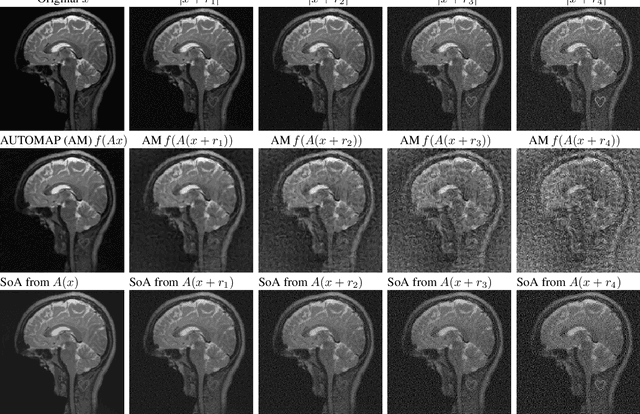

Abstract:Deep learning, due to its unprecedented success in tasks such as image classification, has emerged as a new tool in image reconstruction with potential to change the field. In this paper we demonstrate a crucial phenomenon: deep learning typically yields unstablemethods for image reconstruction. The instabilities usually occur in several forms: (1) tiny, almost undetectable perturbations, both in the image and sampling domain, may result in severe artefacts in the reconstruction, (2) a small structural change, for example a tumour, may not be captured in the reconstructed image and (3) (a counterintuitive type of instability) more samples may yield poorer performance. Our new stability test with algorithms and easy to use software detects the instability phenomena. The test is aimed at researchers to test their networks for instabilities and for government agencies, such as the Food and Drug Administration (FDA), to secure safe use of deep learning methods.